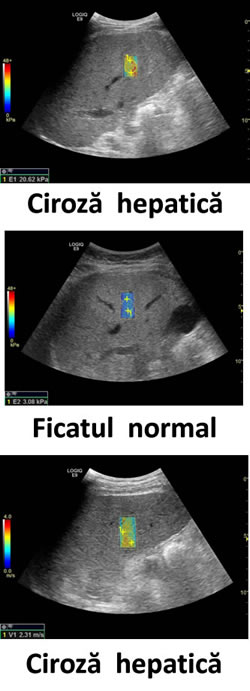

Începînd cu luna februarie, utilizînd cea mai nouă şi performantă versiune a softului, ce efectuează elastografia ficatului cu scop de apreciere gradul de fibroză a parenchimului hepatic.

Soft-ul pentru elastografie este unical, deoarece poate fi utilizată în cazul schimbărilor difuze în parenchimul ficatului şi ajută la aprecierea gradului de fibroză a parenchimului hepatic modificat.

Denumirea internaţională a investigaţiei – SWE (Shear Waves Elastography).

Aprecierea gradului de fibroză - după standardul internaţional METAVIR.

Această investigație este recomandată în hepatite, steatoză hepatică, ciroză hepatică.